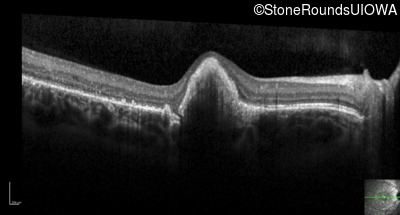

Optical Coherence Tomography - Right - 20/100 +1 sc

Exemplar / OCT Stack

OCT Stack